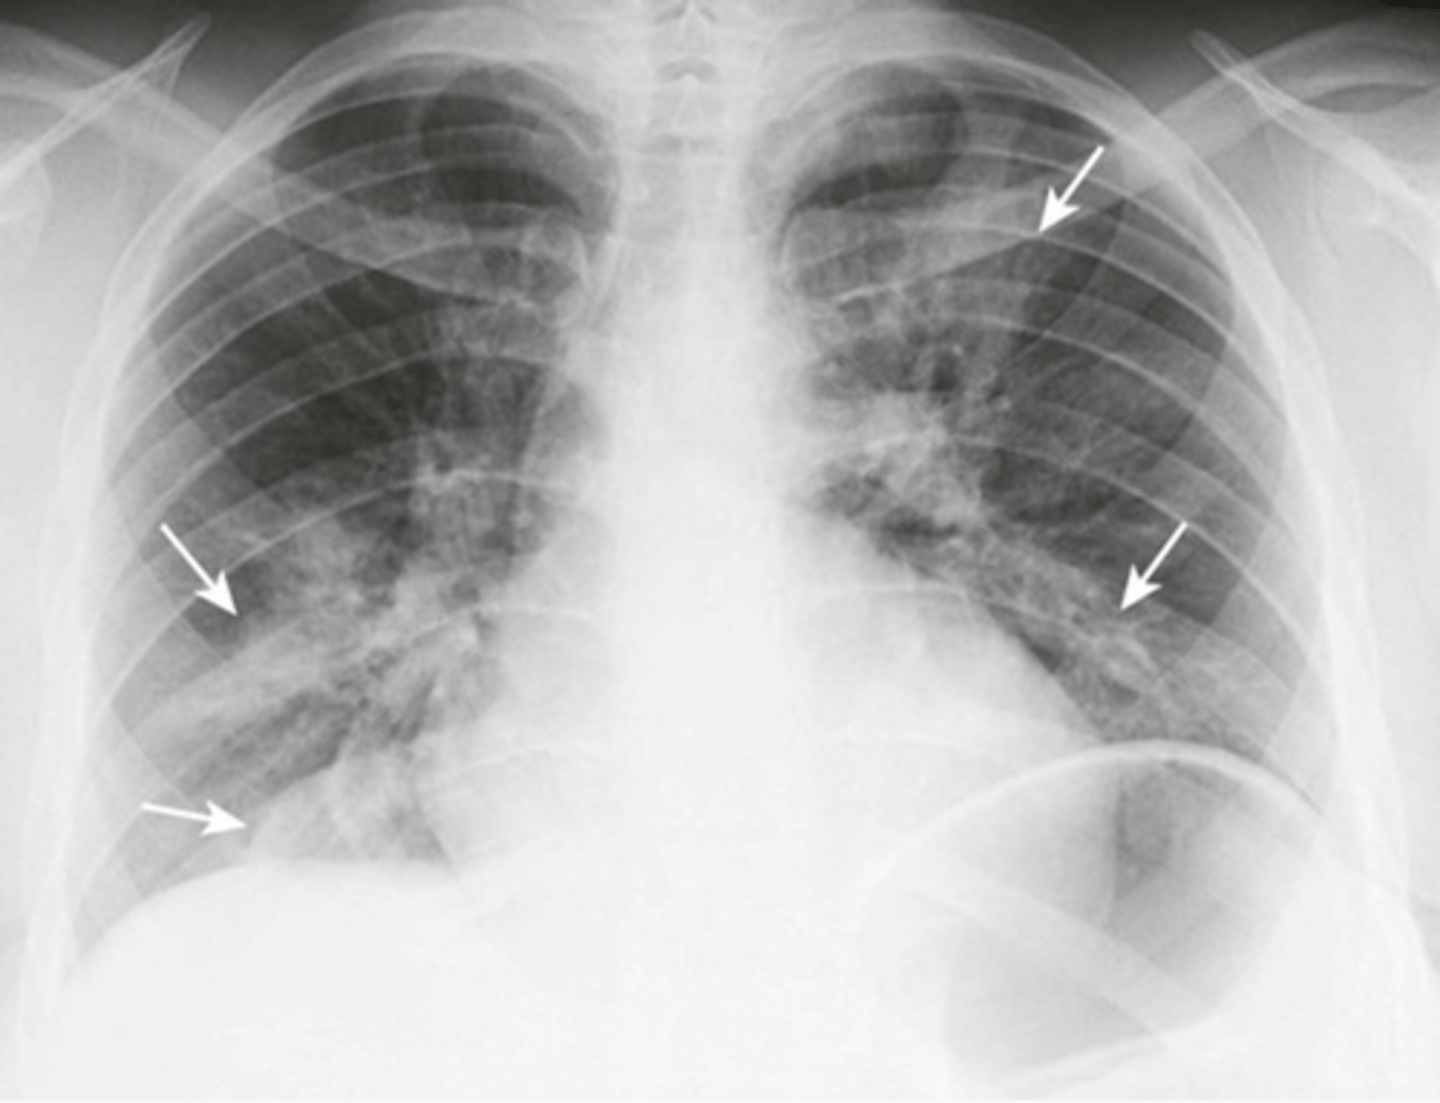

-may have unilateral or patchy b/l areas of consolidation, opacities, bronchial wall thickening, and small pleural effusions

Viral pneumonia and bronchitis imaging

-may see consolidations, ground glass opacities, or nodules

-MC in peripheral and lower zone

-MC bilaterally

Covid on CXR